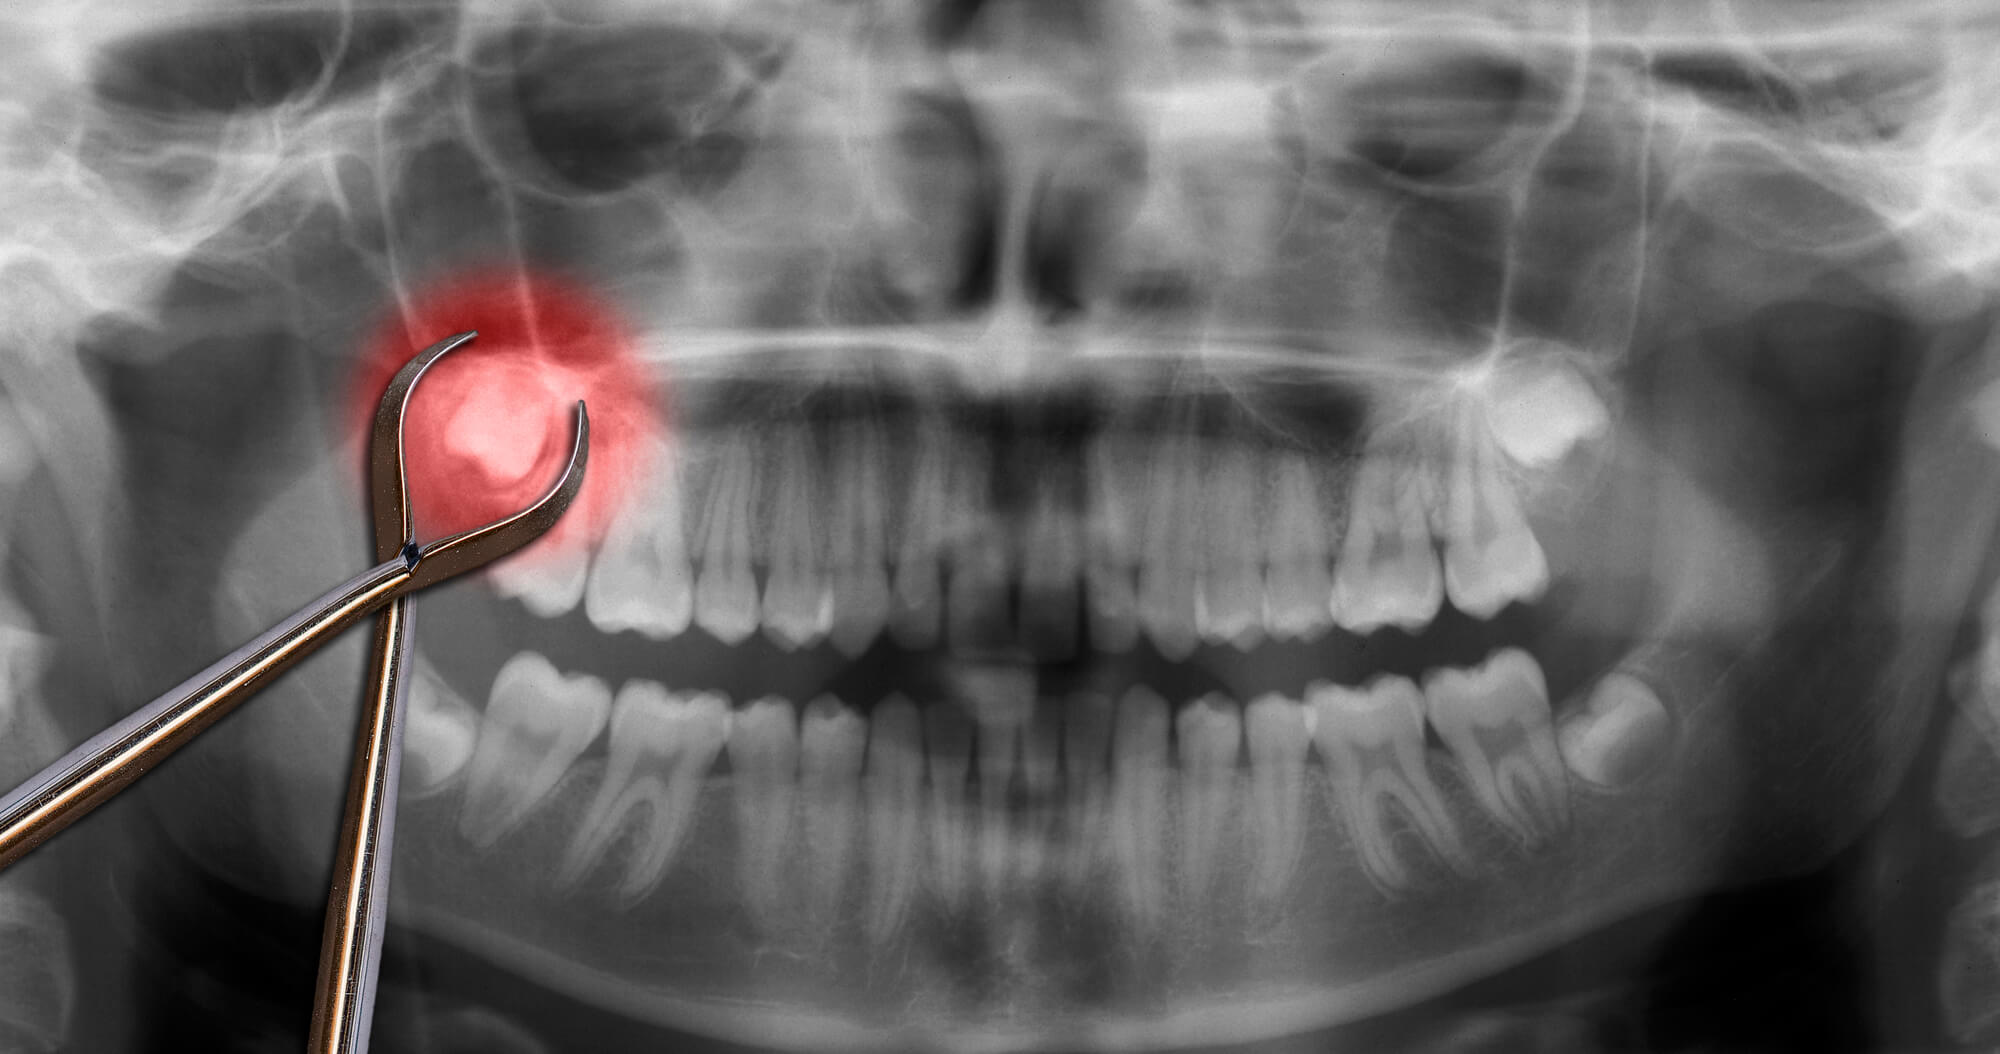

How Safe Is a Tooth Extraction?

Visiting the dentist can be a nerve-wracking experience for many, and the thought of having a tooth pulled might elevate those fears. However, understanding the safety and procedures involved can help ease your concerns. Tooth extraction in Plantation, FL, is a common dental procedure with a high success rate, and when performed by a skilled professional, it is generally safe and effective.

While tooth extractions are generally safe, there are some risks and potential complications to be aware of: